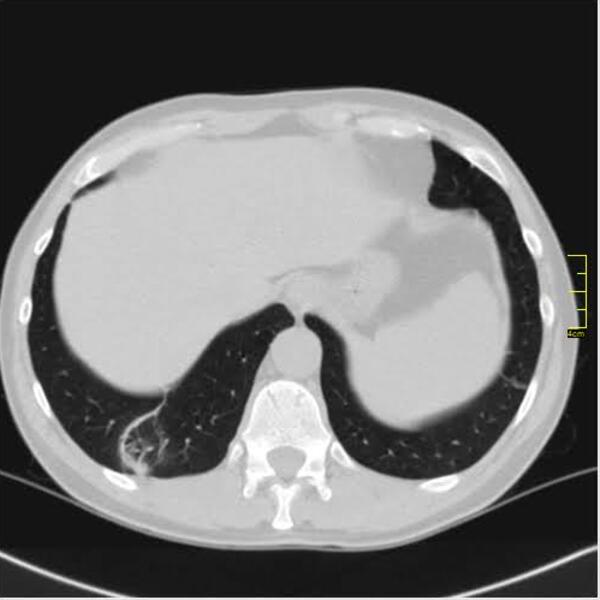

Krenulo je sa divljim sojem. Znamo da je i on imao svoje varijante. Ono što je bilo u samom početku kod nas je ličilo na samu osnovu.

Kada se pogleda pažljivo i deluje divlje, nema neke pravilnosti.

Decembar i januar je dominirao britanski soj. Kada se pogledaju njegove slike vidi se razlika u odnosu na divlji a blizu je onoga koji je bio u leto 2020. godine.

Decembar, januar, februar, mart. 2020/21.

Gustina promena je različita, razlikovala se i klinička slika. retko u decembru ali do marta skoro isključiv.

April 2021. Počinju da dolaze pacijenti koji imaju drugačiji nalaz.

Ono što je karakteristično je to da su ovo nalazi koji su 2. i 3. dana bolesti u I fazi. Znači ne u progresivnoj, već u uvodnoj fazi kada uglavnom nema CT znaka. Fibrozne trake već drugog dana???? Ground glass oko većih grana bronha. Kao da bolest ne može da sačeka, kao da klija gde stigne.